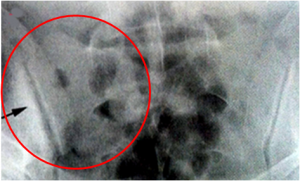

Υμενίτιδα

Ο πεπαχυσμένος υμένας απεικονίζεται υπερηχογραφικά ως ασυμπίεστος, συμπαγής, συνήθως υποηχογενής ενδαρθρικός ιστός, με ή χωρίς την παρουσία αιματικής ροής στο εσωτερικό του στην αιμοδυναμική μελέτη με έγχρωμο και power Doppler (εικ.5,6). Οι Weiner και συν13 έδειξαν καλή ευαισθησία του US στην ανάδειξη της υμενίτιδας στην άκρα χείρα και στον άκρο πόδα, ενώ οι Wiel και συν14 κατέληξαν είναι η μέθοδος αυτή είναι πιο ευαίσθητη από την κλινική εξέταση και τον απλό ακτινολογικό έλεγχο στην ανάδειξη της υμενίτιδας.

Εικόνα 5: Παρατηρείται αυξημένη αγγείωση στο εσωτερικό του πεπαχυσμένου υμένα στη μελέτη με power Doppler (βέλος).